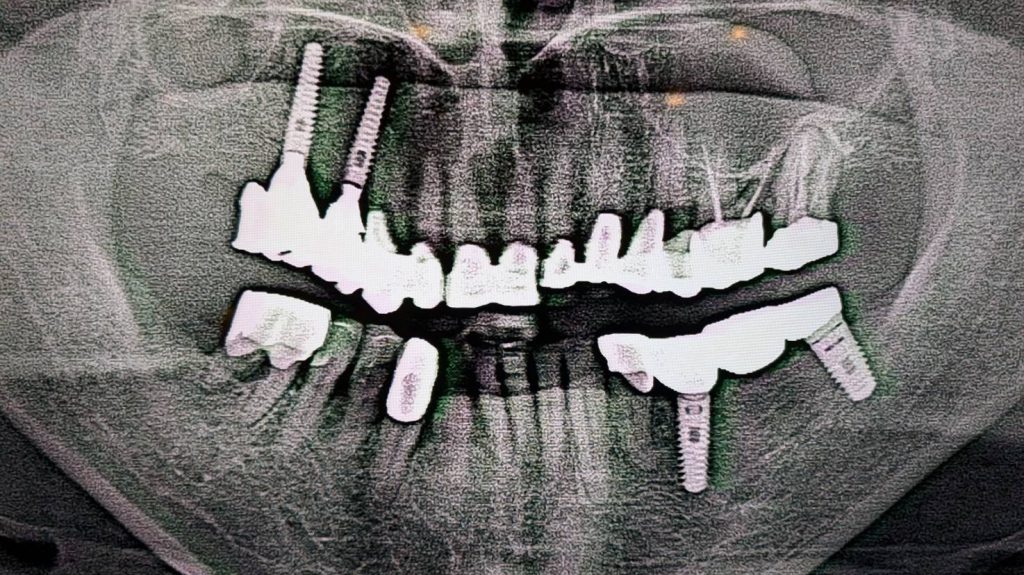

強い歯ぎしりによる咬耗と片噛みの症例

・60代女性

・歯ぎしりの癖で歯が削れてしまい、右上の金属冠(銀歯)が摩耗。

右側で全く噛めなくなり、左側ばかりで噛む「片噛み」の状態でした。

そのため右上と左下にインプラントを埋入し、両側大臼歯部で噛める状態にしました。

●右下と左上下にジルコニア、右上金属(銀歯)が入っていました。

ところが、定期検診でご来院された際に右上の金属がすり減って、全く噛めていない状態ですべて左噛みになっていました。そのため右上の摩耗した金属を取り除き、摩耗に強く精密なジルコニアへと変更しました。また、就寝中の歯ぎしりから歯を守るため、夜間はマウスピースを装着していただきました。